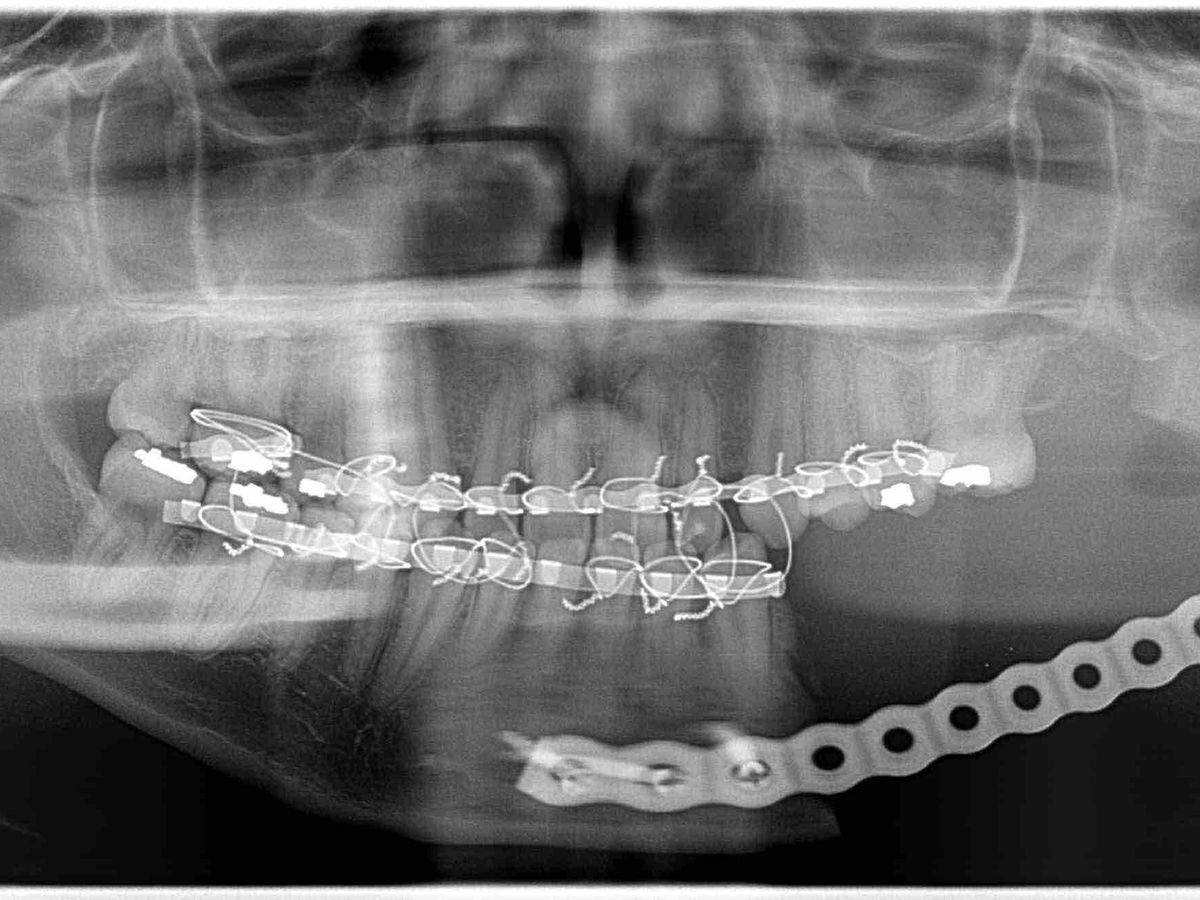

One year later in 2016, the cyst evolved into a tumor which could’ve become cancerous. This was the 3rd time I had to get surgery, and it would be the biggest one so far. The tumor killed 2 more of my teeth, leaving the lower left side of my jaw completely void of teeth. The tumor destroyed most of the bone in my jaw and left me with permanent nerve damage leaving part of my chin and lip completely numb. The surgeon also had to take part of my bone from my hip to transplant into my jaw along with a metal bar to help keep it’s shape, however, this wasn’t a permanent solution. A year went by, and one of the screws in the metal bar in my jaw came undone, which prompted yet another emergency surgery to add a whole new plate.

For the past 4 years, I’ve been unable to chew on the left side of my jaw due to all my missing teeth, I’ve felt pain only being able to chew on one side, my top left teeth are starting to come down, and all of this has severely affected my mental health and quality of life. As you can see in the photo I posted, the lower left side of my jaw is only held together with a metal bar which makes it extremely vulnerable and fragile. After going to countless doctors and traveling far and wide, I’ve learned that reconstructive surgery is my only option and the only place I can get this done is at UCLA. This surgery will involve taking even more bone from my right leg to place in my jaw and be able to get teeth implants. One of the things I love most in life is running and this surgery will weaken my leg, cause me to be bed ridden for 3 months, and will prevent me from running for over a year. Unfortunately, this solution will take an immense financial toll on both my mom and I and we can’t afford it. Our insurance barely helps and isn’t even accepted by 2 out of the 3 doctors who are going to be working on me, so most of the cost has to come out of our pockets. My doctor emphasized that this procedure is medically necessary or else I will have to face even more problems later in life.

One year later in 2016, the cyst evolved into a tumor which could’ve become cancerous. This was the 3rd time I had to get surgery, and it would be the biggest one so far. The tumor killed 2 more of my teeth, leaving the lower left side of my jaw completely void of teeth. The tumor destroyed most of the bone in my jaw and left me with permanent nerve damage leaving part of my chin and lip completely numb. The surgeon also had to take part of my bone from my hip to transplant into my jaw along with a metal bar to help keep it’s shape, however, this wasn’t a permanent solution. A year went by, and one of the screws in the metal bar in my jaw came undone, which prompted yet another emergency surgery to add a whole new plate.

For the past 4 years, I’ve been unable to chew on the left side of my jaw due to all my missing teeth, I’ve felt pain only being able to chew on one side, my top left teeth are starting to come down, and all of this has severely affected my mental health and quality of life. As you can see in the photo I posted, the lower left side of my jaw is only held together with a metal bar which makes it extremely vulnerable and fragile. After going to countless doctors and traveling far and wide, I’ve learned that reconstructive surgery is my only option and the only place I can get this done is at UCLA. This surgery will involve taking even more bone from my right leg to place in my jaw and be able to get teeth implants. One of the things I love most in life is running and this surgery will weaken my leg, cause me to be bed ridden for 3 months, and will prevent me from running for over a year. Unfortunately, this solution will take an immense financial toll on both my mom and I and we can’t afford it. Our insurance barely helps and isn’t even accepted by 2 out of the 3 doctors who are going to be working on me, so most of the cost has to come out of our pockets. My doctor emphasized that this procedure is medically necessary or else I will have to face even more problems later in life.